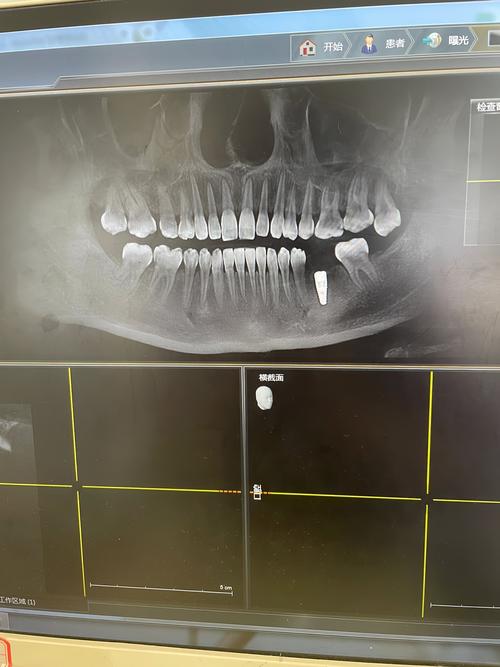

影像学评估标准:术后3个月起,通过根尖片或CBCT检查,若种植体周围骨小梁连续,无透射影,种植体与骨界面模糊(提示骨融合),则提示骨结合完成。

- 影像学检查:术后3个月起拍摄X光片,测量种植体周围骨丧失量(理想情况下<1.5mm),确认骨结合完成。